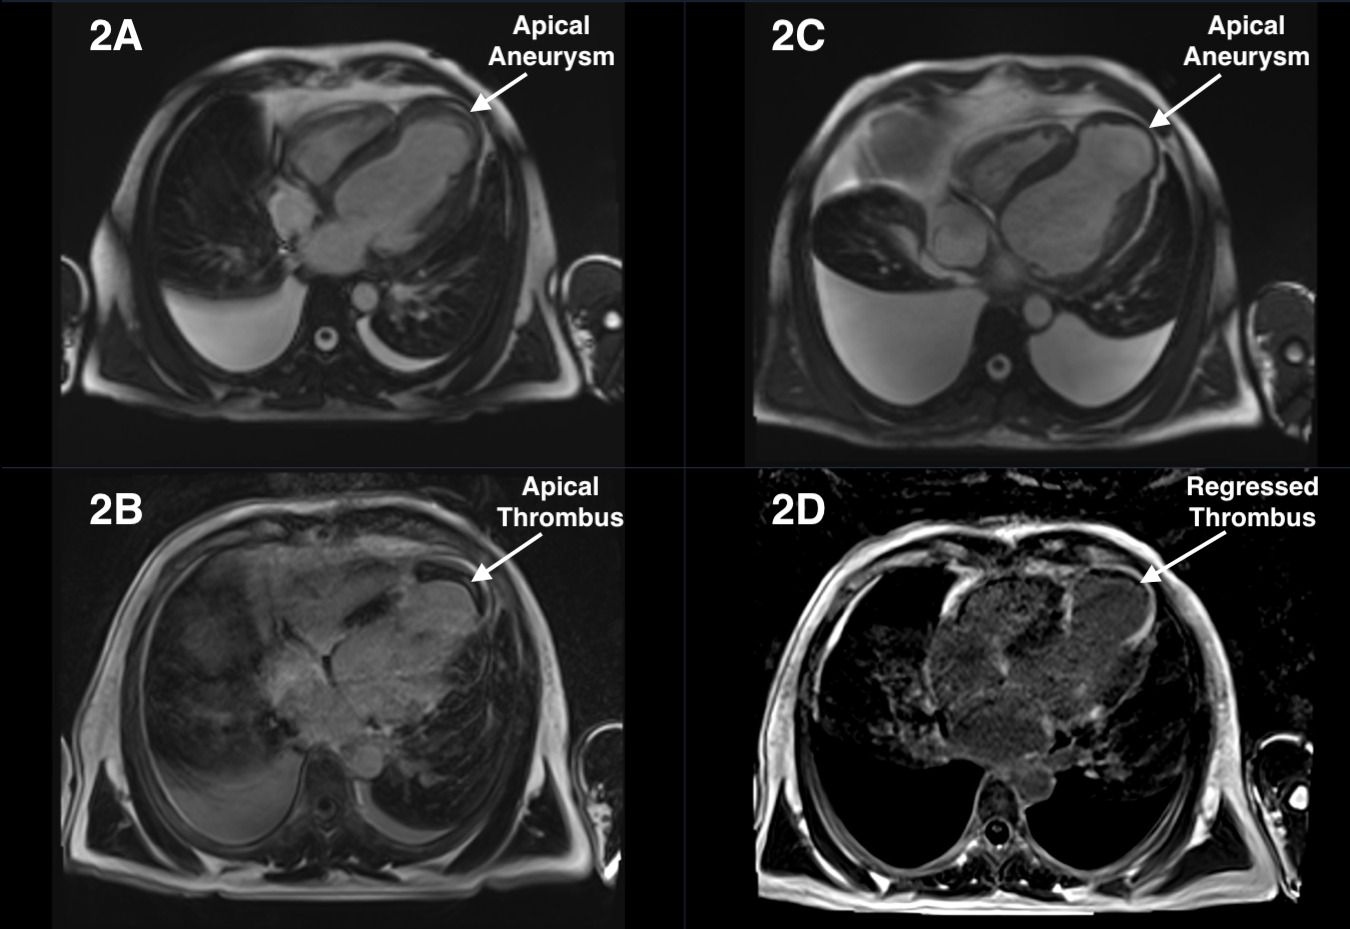

A 51-year-old man with chest pain was admitted to the emergency department. The patient was taken to the coronary angiography lab with a diagnosis of inferior myocardial infarction. The right coronary artery (RCA) was found to be totally occluded. A drug-eluting stent was implanted, and revascularization was achieved (Figure 1A and B). Post-procedure echocardiography (ECHO) showed a suspicious appearance consistent with ventricular septal rupture in the apical septum region (Figure 1C and D; Video). The patient was hemodynamically stable and cardiac magnetic resonance imaging (MRI) was performed. Cardiac MRI revealed aneurysmatic enlargement in the cardiac apical region and a 58 x 14-mm thrombus surrounding the wall of the aneurysm much like a rim (Figure 2A and B). The patient was administered warfarin, an oral vitamin K antagonist, and was anticoagulated. At 2-month follow-up, we performed a control cardiac MRI and determined that the thrombus had significantly regressed (Figure 2C and D).